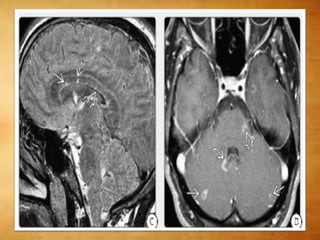

BALO CONCENTRIC SCLEROSIS

• Concentric rings of demyelination/myelin

preservation

○ Resemble tree trunk or onion bulb

○ Solitary > multifocal

• Acute onset and rapid clinical deterioration

• "Whirlpool" hyperintense concentric rings on

T2WI

○ Minimal mass effect, edema

• Actively demyelinating layers enhance

SCHILDER DISEASE • Myelinoclasticdiffuse sclerosis ○ Rare acute/subacute demyelinating disorder ○ Lesions may resolve; 15% progress to MS • Young adults , female preponderance • Clinical features atypical for MS, ADEM ○ CSF normal ○ No history of fever, flu, vaccination • Solitary > multifocal lesions • Lesions look like tumefactive MS • Differential diagnosis: Neoplasm and Abscess

BALO CONCENTRIC SCLEROSIS •Concentric rings of demyelination/myelin preservation ○ Resemble tree trunk or onion bulb ○ Solitary > multifocal • Acute onset and rapid clinical deterioration • "Whirlpool" hyperintense concentric rings on T2WI ○ Minimal mass effect, edema • Actively demyelinating layers enhance